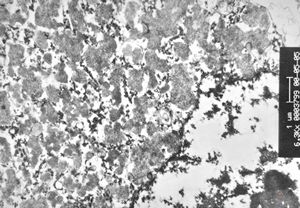

M, 44y. | Gaucher disease … spleen